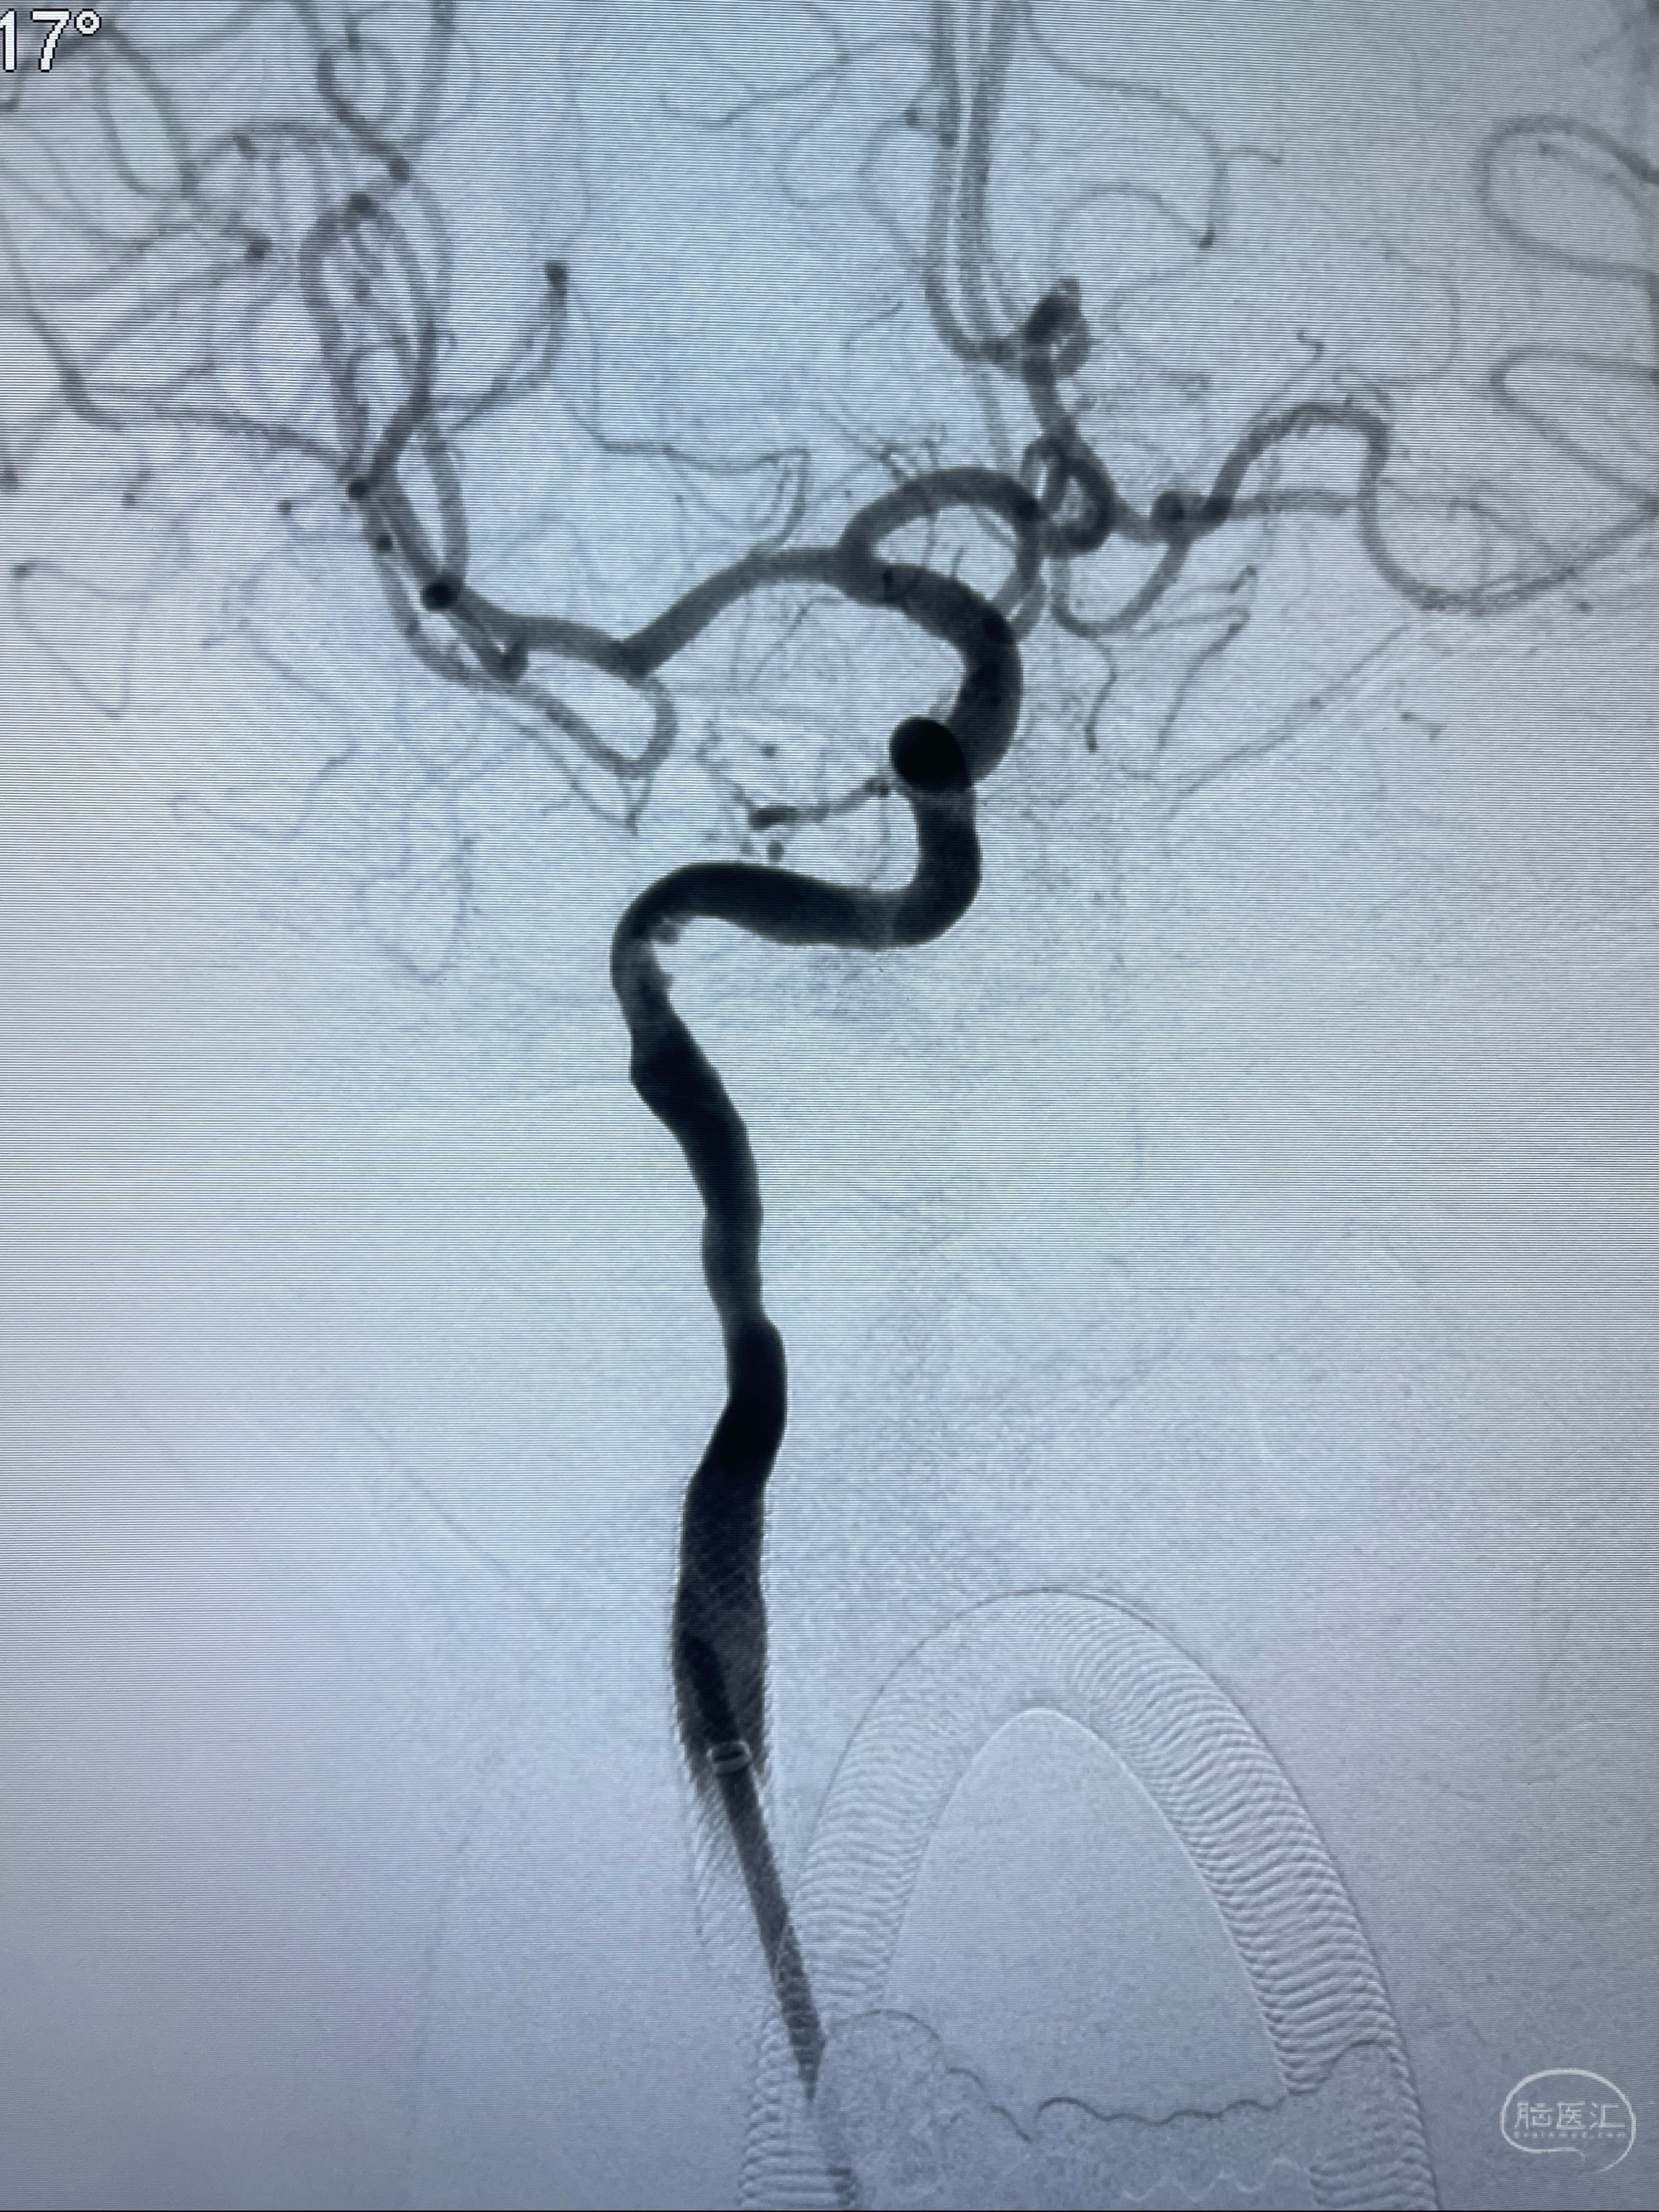

2023-07-10DSA:右侧颈内动脉岩骨段夹层伴中偏重度狭窄改变,左侧颈总动脉闭塞、右侧颈外动脉由右侧肋颈干甲颈干吻合代偿

箭头所示为颈内动脉岩骨段重度狭窄,结合MRI,考虑为肿瘤侵犯右侧颈内动脉

箭头以近至支架段管腔不规则狭窄

MRI:显示肿瘤侵犯右侧颈内动脉岩骨段上下,向下至原颈内动脉支架远心段,向上至颅底

经导引导管造影显示支架远端颈内动脉不规则狭窄伴局部充盈缺损,同时行全身肝素化5ml